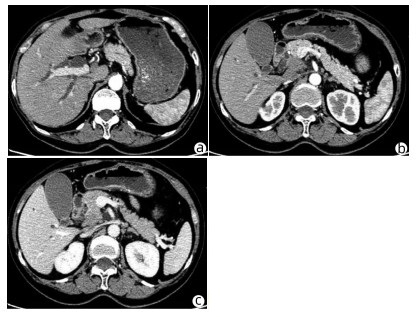

Clinical effect of simultaneous surgical resection of hepatic and pancreatic lesions versus systemic chemotherapy in treatment of resectable pancreatic cancer with liver metastasis

Tianqiang JIN, Chaoliu DAI, Feng XU

2022, 38(3): 622-628. DOI: 10.3969/j.issn.1001-5256.2022.03.023

Abstract(1384) HTML (1170) PDF (2734KB)(54)

Abstract:

Objective  To investigate the clinical effect of simultaneous surgical resection of hepatic and pancreatic lesions versus systemic chemotherapy in treatment of resectable pancreatic cancer with liver metastasis (PCLM).  Methods  A retrospective analysis was performed for related data of the patients with PCLM who were admitted to Shengjing Hospital of China Medical University from January 2013 to May 2020, and the patients with resectable PCLM were screened out and then divided into surgery group and chemotherapy group. The propensity score matching (PSM) method was used to reduce the impact of data bias and confounding factors. The independent samples t-test or the Mann- Whitney U test was used for comparison of continuous data between two groups, and the chi-square test was used for comparison of categorical data between two groups. The Kaplan-Meier method was used to calculate survival time, and the log-rank test was used for evaluation. The univariate and multivariate Cox regression models were used to investigate the independent risk factors for survival.  Results  A total of 56 patients with resectable PCLM were screened out, with 33 patients in the surgery group and 23 patients in the chemotherapy group, and there were 15 patients in each group after PSM. The surgery group had a significantly shorter median overall survival time than the chemotherapy group before PSM (6.6 months vs 10.4 months, χ2=4.476, P=0.034) and after PSM (6.4 months vs 10.5 months, χ2=4.309, P=0.038). The multivariate Cox regression analysis showed that poorly differentiated tumor (hazard ratio [HR]=4.945, 95% confidence interval [CI]: 1.980-12.348, P=0.001) and absence of postoperative chemotherapy (HR=3.670, 95%CI: 1.437-9.376, P=0.007) were independent risk factors for poor prognosis in patients with PCLM.  Conclusion  Compared with chemotherapy, simultaneous surgical resection of hepatic and pancreatic lesions fails to prolong the overall survival time of patients with resectable PCLM. Patients with poorly differentiated tumor and those without postoperative chemotherapy tend to have poor prognosis.